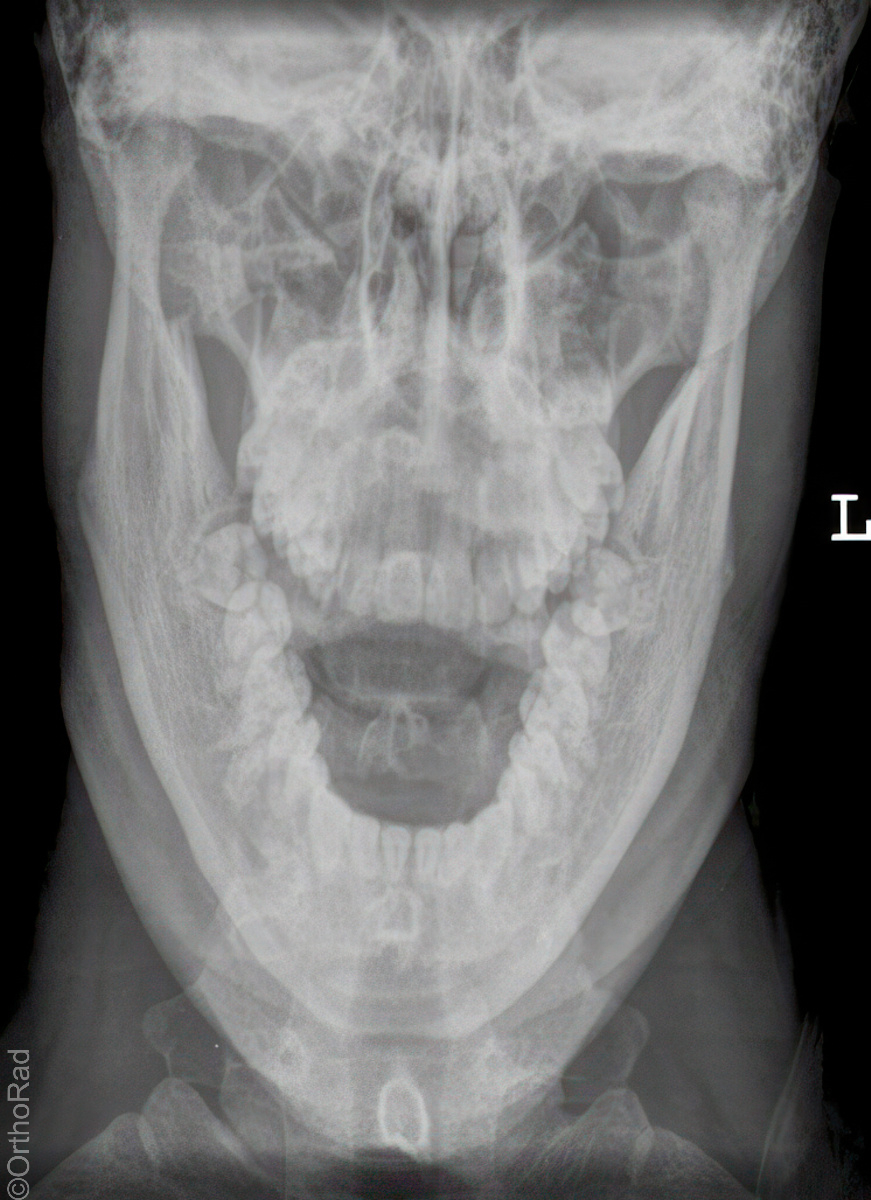

Nasennebenhöhlen (NNH)

Technik

• FDA: 1,15 m

• Ausgangsformat: Detektor oder 18/24 hoch

• mit Raster

Indikation

Sinusitis, Z. n. Osteosynthese

Lagerung

sitzend mit Gesicht zum Stativ

Hände festhaltend am Stativ

Rücken gerade

Mund weit geöffnet

Kinn liegt auf, Nase schwebt

Kopf anheben bis obere Zahnreihe und 1 QF über Ohr-Rand eine Linie bilden

Zentralstrahl

Querstrahl: 1 QF über oberen Ohrrand & Oberlippe

Längsstrahl: Medianebene

Einblendung

lateral auf Augenwinkel, cranial: auf Haaransatz

Anmerkung

Besonders auf symmetrische Lagerung achten. Im Sitzen ist evtl. Flüssigkeitsspiegel gut beurteilbar.

Qualitätskriterien

Symmetrische Darstellung des Gesichtsschädels: seitengleiche Distanz zwischen lateralem Rand der Augenhöhle und äußerer Schädelkontur. Die Pyramidenoberkanten kommen unmittelbar unterhalb des Kieferhöhlenbodens zum Liegen, also in die obere Zahnreihe, sodass die Kieferhöhlen überlagerungsfrei zur Darstellung kommen.